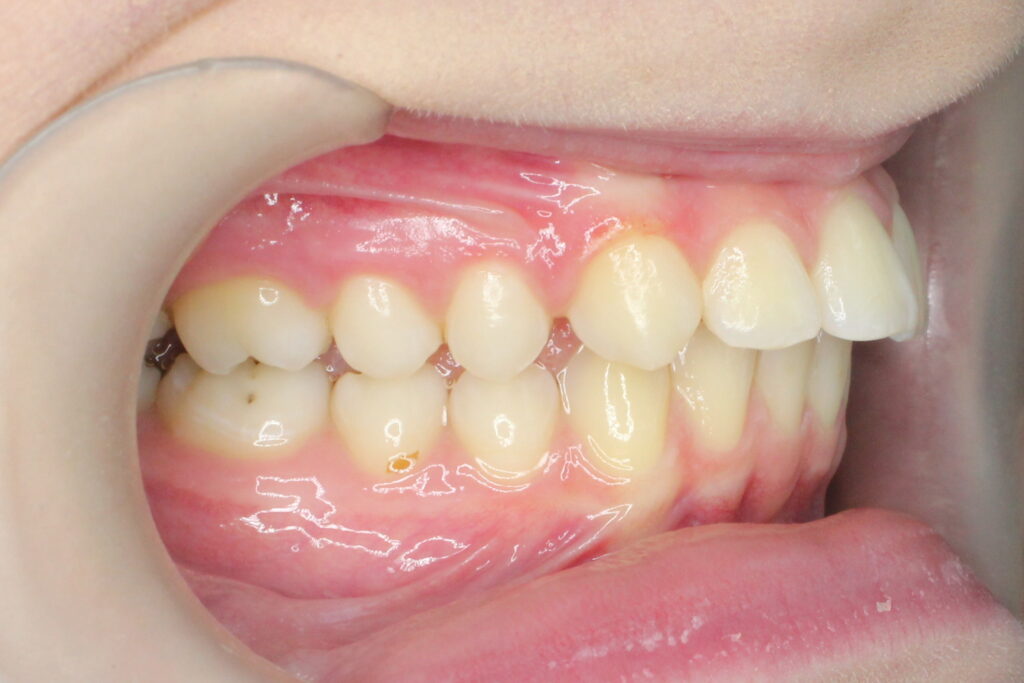

Ситуация до лечения

Диагноз: дистальный прикус, сужение, удлинение верхнего зубного ряда, скученность фронтальной группы зубов на нижней челюсти. Лечение проводилось самолигирующей брекет-системой Damon Q, срок лечения составил 2 года и 2 месяца.

Ситуация до лечения брекетами